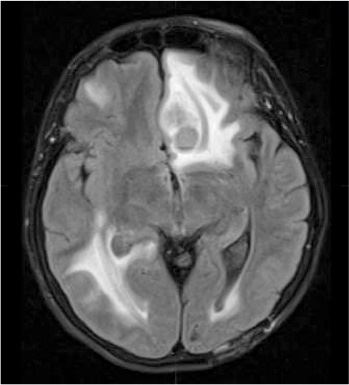

На снимках моего мозга четко виднелась россыпь черных точек, каждая размером с изюминку, – всего около восемнадцати, по словам доктора Аткинса. Самые крупные опухоли находились в лобной и теменной долях, но были и другие – в височной, в затылочной доле, в базальных ганглиях, расположенных в глубине мозга, которые помогают нам координировать движения. Позже Кася рассказала, что на снимках мой мозг был похож на ломоть хлеба с изюмом.

Самая большая опухоль, размером с миндалину, по словам доктора, находилась в лобной доле.

Иллюстрация к книге — Потерявшая разум. Откровенная история нейроученого о болезни, надежде и возвращении [i_006.jpg]

Снимок моего мозга, сделанный 19 июня, на котором доктор Аткинс обнаружил новые опухоли (круглые образования) и обширный отек (белые области). Самая заметная опухоль – в верхней части снимка в префронтальной коре

– Также на снимках видны несколько смазанных белых областей, которые указывают на сильнейший отек мозга.